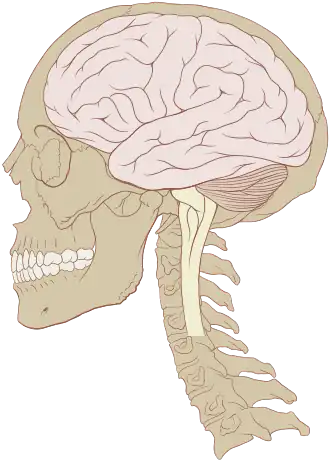

The human brain is the central organ of the nervous system, and with the spinal cord, comprises the central nervous system. It consists of the cerebrum, the brainstem and the cerebellum. The brain controls most of the activities of the body, processing, integrating, and coordinating the information it receives from the sensory nervous system. The brain integrates sensory information and coordinates instructions sent to the rest of the body.

The cerebrum, the largest part of the human brain, consists of two cerebral hemispheres. Each hemisphere has an inner core composed of white matter, and an outer surface – the cerebral cortex – composed of grey matter. The cortex has an outer layer, the neocortex, and an inner allocortex. The neocortex is made up of six neuronal layers, while the allocortex has three or four. Each hemisphere is divided into four lobes – the frontal, parietal, temporal, and occipital lobes. The frontal lobe is associated with executive functions including self-control, planning, reasoning, and abstract thought, while the occipital lobe is dedicated to vision. Within each lobe, cortical areas are associated with specific functions, such as the sensory, motor, and association regions. Although the left and right hemispheres are broadly similar in shape and function, some functions are associated with one side, such as language in the left and visual-spatial ability in the right. The hemispheres are connected by commissural nerve tracts, the largest being the corpus callosum.

The cerebrum is connected by the brainstem to the spinal cord. The brainstem consists of the midbrain, the pons, and the medulla oblongata. The cerebellum is connected to the brainstem by three pairs of nerve tracts called cerebellar peduncles. Within the cerebrum is the ventricular system, consisting of four interconnected ventricles in which cerebrospinal fluid is produced and circulated. Underneath the cerebral cortex are several structures, including the thalamus, the epithalamus, the pineal gland, the hypothalamus, the pituitary gland, and the subthalamus; the limbic structures, including the amygdalae and the hippocampi, the claustrum, the various nuclei of the basal ganglia, the basal forebrain structures, and three circumventricular organs. Brain structures that are not on the midplane exist in pairs; for example, there are two hippocampi and two amygdalae.

The adult human brain weighs on average about 1.2–1.4 kg (2.6–3.1 lb) which is about 2% of the total body weight,[2][3] with a volume of around 1260 cm3 in men and 1130 cm3 in women.[4] There is substantial individual variation,[4] with the standard reference range for men being 1,180–1,620 g (2.60–3.57 lb)[5] and for women 1,030–1,400 g (2.27–3.09 lb).[6]

The cerebrum, consisting of the cerebral hemispheres, forms the largest part of the brain and overlies the other brain structures.[7] The outer region of the hemispheres, the cerebral cortex, is grey matter, consisting of cortical layers of neurons. Each hemisphere is divided into four main lobes – the frontal lobe, parietal lobe, temporal lobe, and occipital lobe.[8] Three other lobes are included by some sources which are a central lobe, a limbic lobe, and an insular lobe.[9] The central lobe comprises the precentral gyrus and the postcentral gyrus and is included since it forms a distinct functional role.[9][10]

The brainstem, resembling a stalk, attaches to and leaves the cerebrum at the start of the midbrain area. The brainstem includes the midbrain, the pons, and the medulla oblongata. Behind the brainstem is the cerebellum (Latin: little brain).[7]